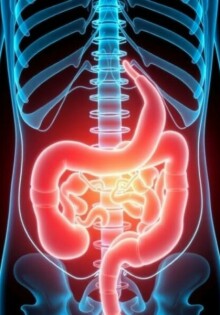

Apendicitis y seguro médico: qué cubre, qué tramites debes conocer y cómo proteger tu bolsillo

El rol de las enfermeras en el postoperatorio: guardianas del proceso de recuperación